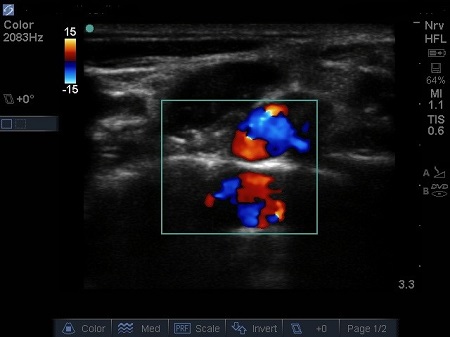

Hypoechoic vessels may be seen among the brachial plexus nerves (also round hypoechoic structures). Because they have similar appearance, it is important to differentiate them (colour Doppler MUST be used) (16). See Fig. 9.

Fig. 9. Doppler highlighting subclavian artery with dorsal scapular artery passing posteriorly through brachial plexus.